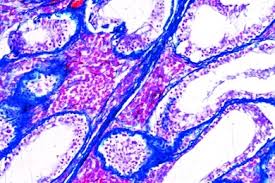

The primary risk factor for cervical cancer is human papillomavirus (hpv) infection. The uterus (or womb) is. Cancer of the cervix uteri. Cancer incidence and mortality statistics worldwide and by region. Endometrial cancer is cancer of the uterus. The normal ectocervix (the portion of the uterus extending into the vagina). examples of lymphatic metastasis diagnosis in cancer cervicis uteri stages i and ii. / american brachytherapy society consensus guidelines for locally advanced carcinoma of the cervix. Cervical cancer is the fourth most common cancer in women worldwide. The progression to cervical cancer begins with the development of precancerous changes in normal cells. Treatment of early stages of cervical cancer. Cervical cancer is cancer that starts in the cervix, the narrow opening into the uterus from the vagina. Early on, typically no symptoms are seen.

Cervical carcinoma confined to uterus (extension to corpus should be disregarded). The primary risk factor for cervical cancer is human papillomavirus (hpv) infection. The endocervix is the opening of the cervix that leads into the uterus. Cancer of the cervix uteri. Treatment of early stages of cervical cancer. Cervical cancer happens when the cells of your cervix change. examples of lymphatic metastasis diagnosis in cancer cervicis uteri stages i and ii. Cancer is a disease in which cells in the body grow out of control. The cancer might invade other you could also have a hysterectomy, in which your doctor removes your uterus. Back to womb (uterus) cancer. They also do tests to learn if cancer has spread to another part of the body from where it started. Vishwanathan a.n., beriwal s., de los santos j.f. Learn about the causes, symptoms, and treatments.